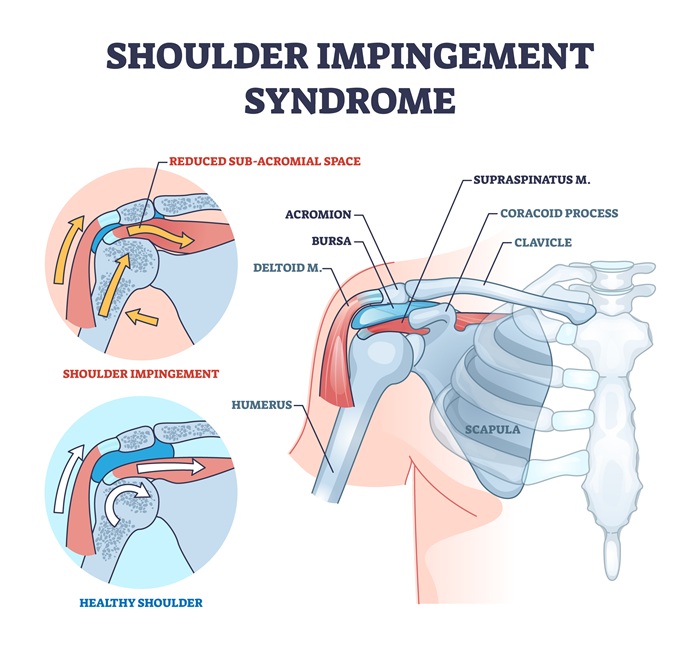

Shoulder impingement syndrome is one of the most common—and most misunderstood—sources of shoulder pain in adults. The shoulder relies on complex coordination between bones, muscles, tendons, and fluid-filled sacs called bursae to allow effortless movement. At the heart of impingement is a vital structure: the subacromial space. This narrow passage, sandwiched between the acromion (the high point of the shoulder blade) above and the head of the humerus below, houses the critically important rotator cuff tendons and the subacromial bursa.

In a healthy shoulder, these soft tissues slide freely as you lift, rotate, or reach with your arm. However, when this space becomes crowded by swollen tendons, inflamed bursa, bone spurs, or shape changes in the acromion, tissues get pinched, resulting in sharp pain, inflammation, and loss of function.

What Actually Gets "Impinged"? Exploring the Subacromial Space

- Rotator cuff tendons: Especially the supraspinatus, which passes beneath the acromion when lifting the arm.

- Subacromial bursa: This lubricating sac cushions the rotator cuff from the bones above.

- Biceps tendon: Less commonly, this structure can also become entrapped.

Anatomic variations, such as a hooked or downward-tilting acromion or the formation of bone spurs with age and arthritis, further crowd this pathway. In some individuals, genetics play a significant role, predisposing people to impingement even without major injury.